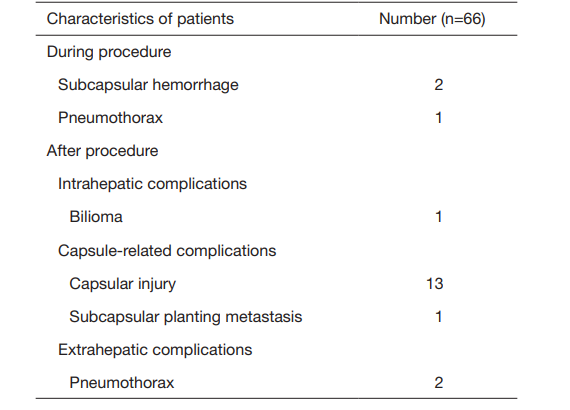

部分结果:

① 在我们的研究中,技术成功率为100%。动态增强MR检查随访1个月,66例患者首次技术有效率为65例(98.5%),MR影像学未发现外周脏器损伤。中位随访时间14个月(范围2-28个月)。高危部位肝癌局部肿瘤进展率曲线:6、9、15和24个月的累积局部肿瘤进展率分别为10.2%、16.5%、20.9%和30.5%。